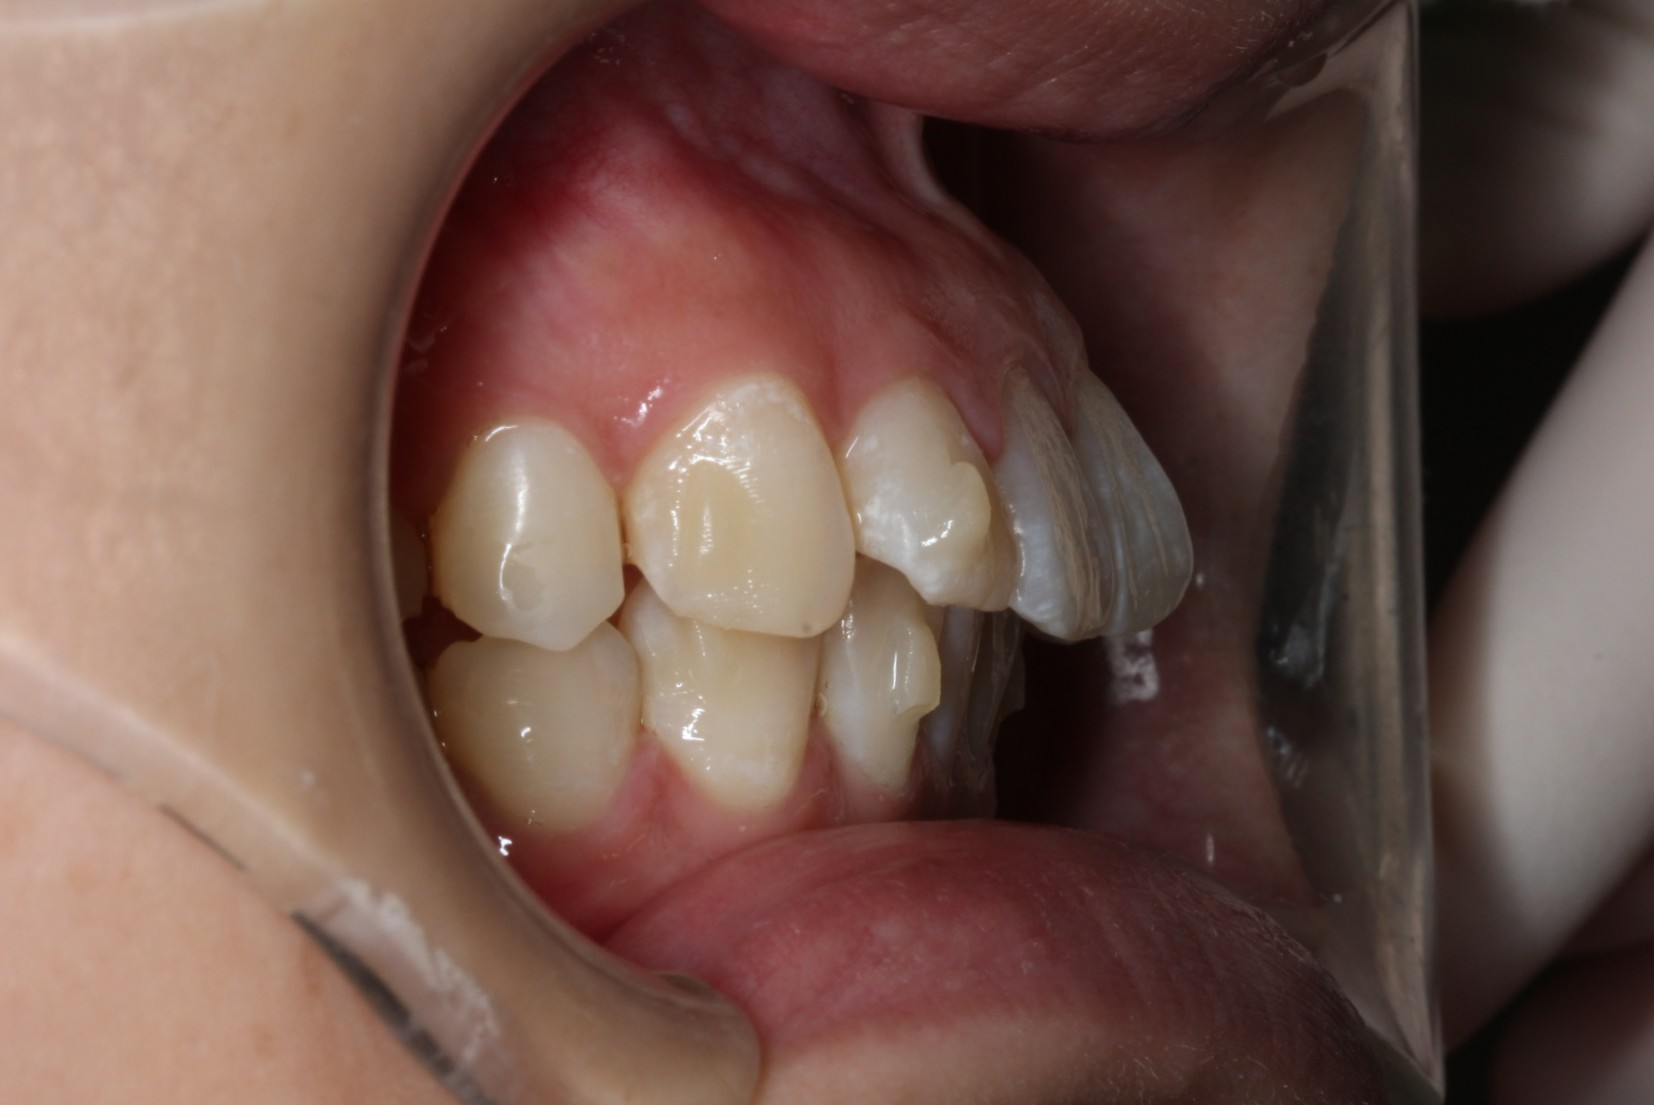

矯正術前:右側

矯正術後:右側